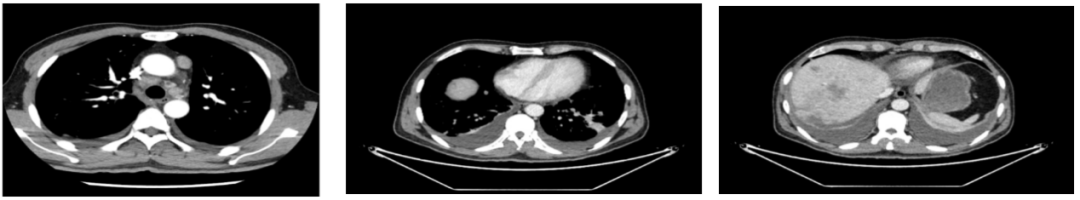

2020年4月复查:持续PR

肿瘤标志物:均正常

肝功能正常。

增强CT示:肝硬化

肝异常强化灶

考虑酒精性肝硬化可能性大,未基线使用替吉奥维持治疗。

胃癌并肝转移化疗后,肝内转移灶大致同期;

慢性肝病,脾大、门脉高压(食管下段-胃底静脉曲张);

双肾小囊肿;

右肺中叶外侧段、左肺上叶下舌段及右肺下叶后基底段慢性炎症;

右肺上叶前段实性微小结节,炎性结节?建议定期复查;

纵隔淋巴结转移瘤,复查大致同前。